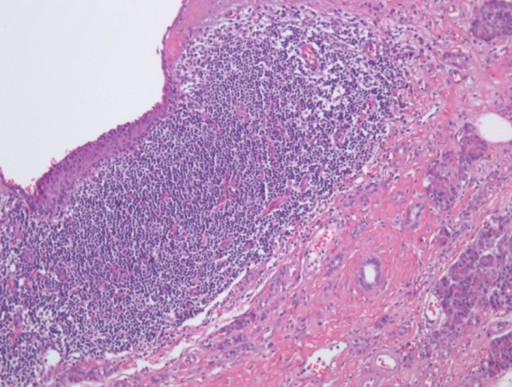

A 63-year-old man with a previous history of colon cancer, resected 3 years earlier, presented for a routine clinical follow-up. Physical examination and past medical history were unremarkable, except for an appendectomy at the age of 15. The patient had had a history of intermittent and mild left upper quadrant abdominal pain not associated with meals before a resection for colonic cancer; CA 19-9, CEA and amylase were unremarkable. There was no body weight loss or fever, and the patient had no previous history of pancreatitis. An abdominal ultrasound was performed which showed a 7 cm non homogeneous anechoic mass at the level of the pancreatic tail. An MR scan was subsequently obtained which confirmed the presence of a 7x4 cm lesion at the level of the pancreatic tail, close to the splenic hylum. This lesion showed a complex structure with multiple sub-centimeter nodules within it. In particular, the lesion was homogeneously hypointense on the pre-contrast T1-weighted MR images (Figure 1), showing a mild rim of enhancement after intravenous contrast administration while maintaining the hypointensity of the central core constant (Figure 2); on T2-weighted MR images, the pancreatic mass had a "cheerios-like" appearance, showing multiple small nodules with a central hypointensity and peripheral hyperintensity; a fluid-level was also present at the bottom of the lesion (Figures 3 and 4), most likely reflecting the inflammatory changes of the lesion. The patient subsequently underwent a distal pancreatectomy and splenectomy (due to the proximity of the lesion to the splenic hylum). Histological examination demonstrated the benign nature of the lesion consisting of a pancreatic lymphoepithelial cyst. The surface of the cyst was smooth, the lesion was filled with keratinous material and the walls were lined with stratified squamous epithelium which was surrounded by a layer of lymphoid tissue composed of small lymphocytes, plasma cells and germinal centers, without signs of atypia (Figure 5). The periphery was composed of normal pancreatic tissue. The postoperative course was uneventful and the patient was discharged from the hospital 10 days after the surgical intervention.

Figure 5. Histopathological findings of the cyst: stratified squamous epithelium with adjacent lymphoid infiltrate, without signs of atypia. |

Lymphoepithelial cysts of the pancreas are rare lesions and fewer than 100 cases have been reported in the English literature. The etiology is unclear; it has been hypothesized that these lesions represent enlarged epithelial inclusions in a peripancreatic lymph node which has undergone a squamous metaplasic phenomenon [7]. Other authors have identified these cysts in ectopic pancreatic tissue [8, 9]. Histologically, lymphoid epithelial cysts are lined with squamous epithelium without atypia. The wall of the cyst contains lymphocytes usually accompanied by germinal centers. It has also been hypothesized that these lesions represent benign epithelial inclusions, embedded in the pancreas or branchial cleft cysts fused with the pancreatic remnant during embryogenesis [10].